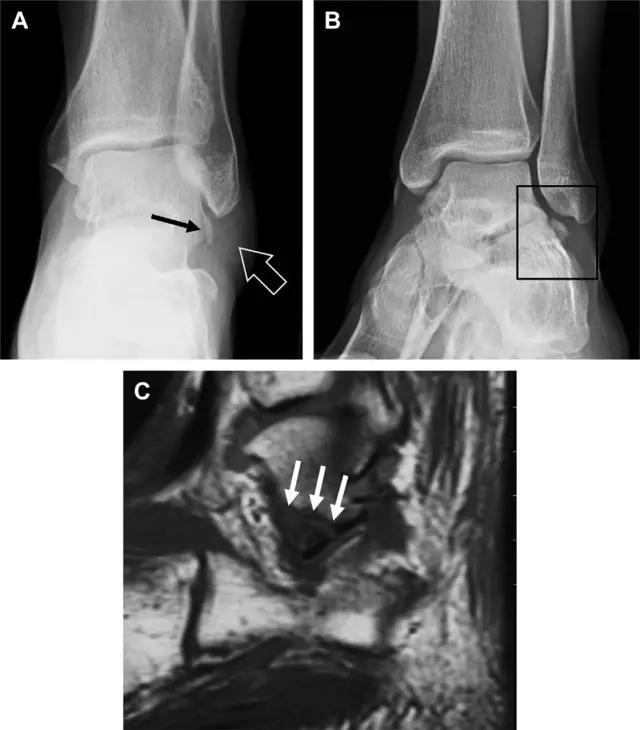

19 距骨后突骨折

距骨后突有内侧结节和外侧结节,距骨后突内侧结节撕脱性骨折常发生在背屈内旋的*力暴**作用下。严重跖屈时,胫骨后缘和跟骨挤压距骨后突外侧结节呈楔形,易发生粉碎性骨折。这些骨折细微且需与三角骨鉴别。侧位片观察距骨后突骨折最佳,常规拍片很难发现,当高度怀疑这种骨折又没法做 CT 时,建议加做多个角度的外旋斜位片(图 5)。

图 5 距骨后突骨折。侧位片(A)和 MRI 矢状位 T1 加权像(B)均示后外侧突的简单骨折(箭头),再次阅片时才发现 X 线片上的骨折;侧位片(C)和 CT 横断面图像示后内侧突的粉碎型骨折(箭头)